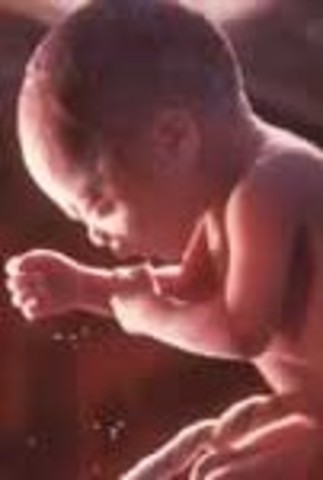

• Week Twenty Nine: Movement is more forceful

Week Twenty Nine: Movement is more forceful

Baby's muscles and lungs are continuing to mature. The fetus can taste and respond to pain. The milk teeth have developed under the gums.

• Week Thirty: Baby puts on pounds

Week Thirty: Baby puts on pounds

The wrinkled skin is becoming smoother now. In boys, the testicles have moved down to the groin. The baby controls its own body temperature.